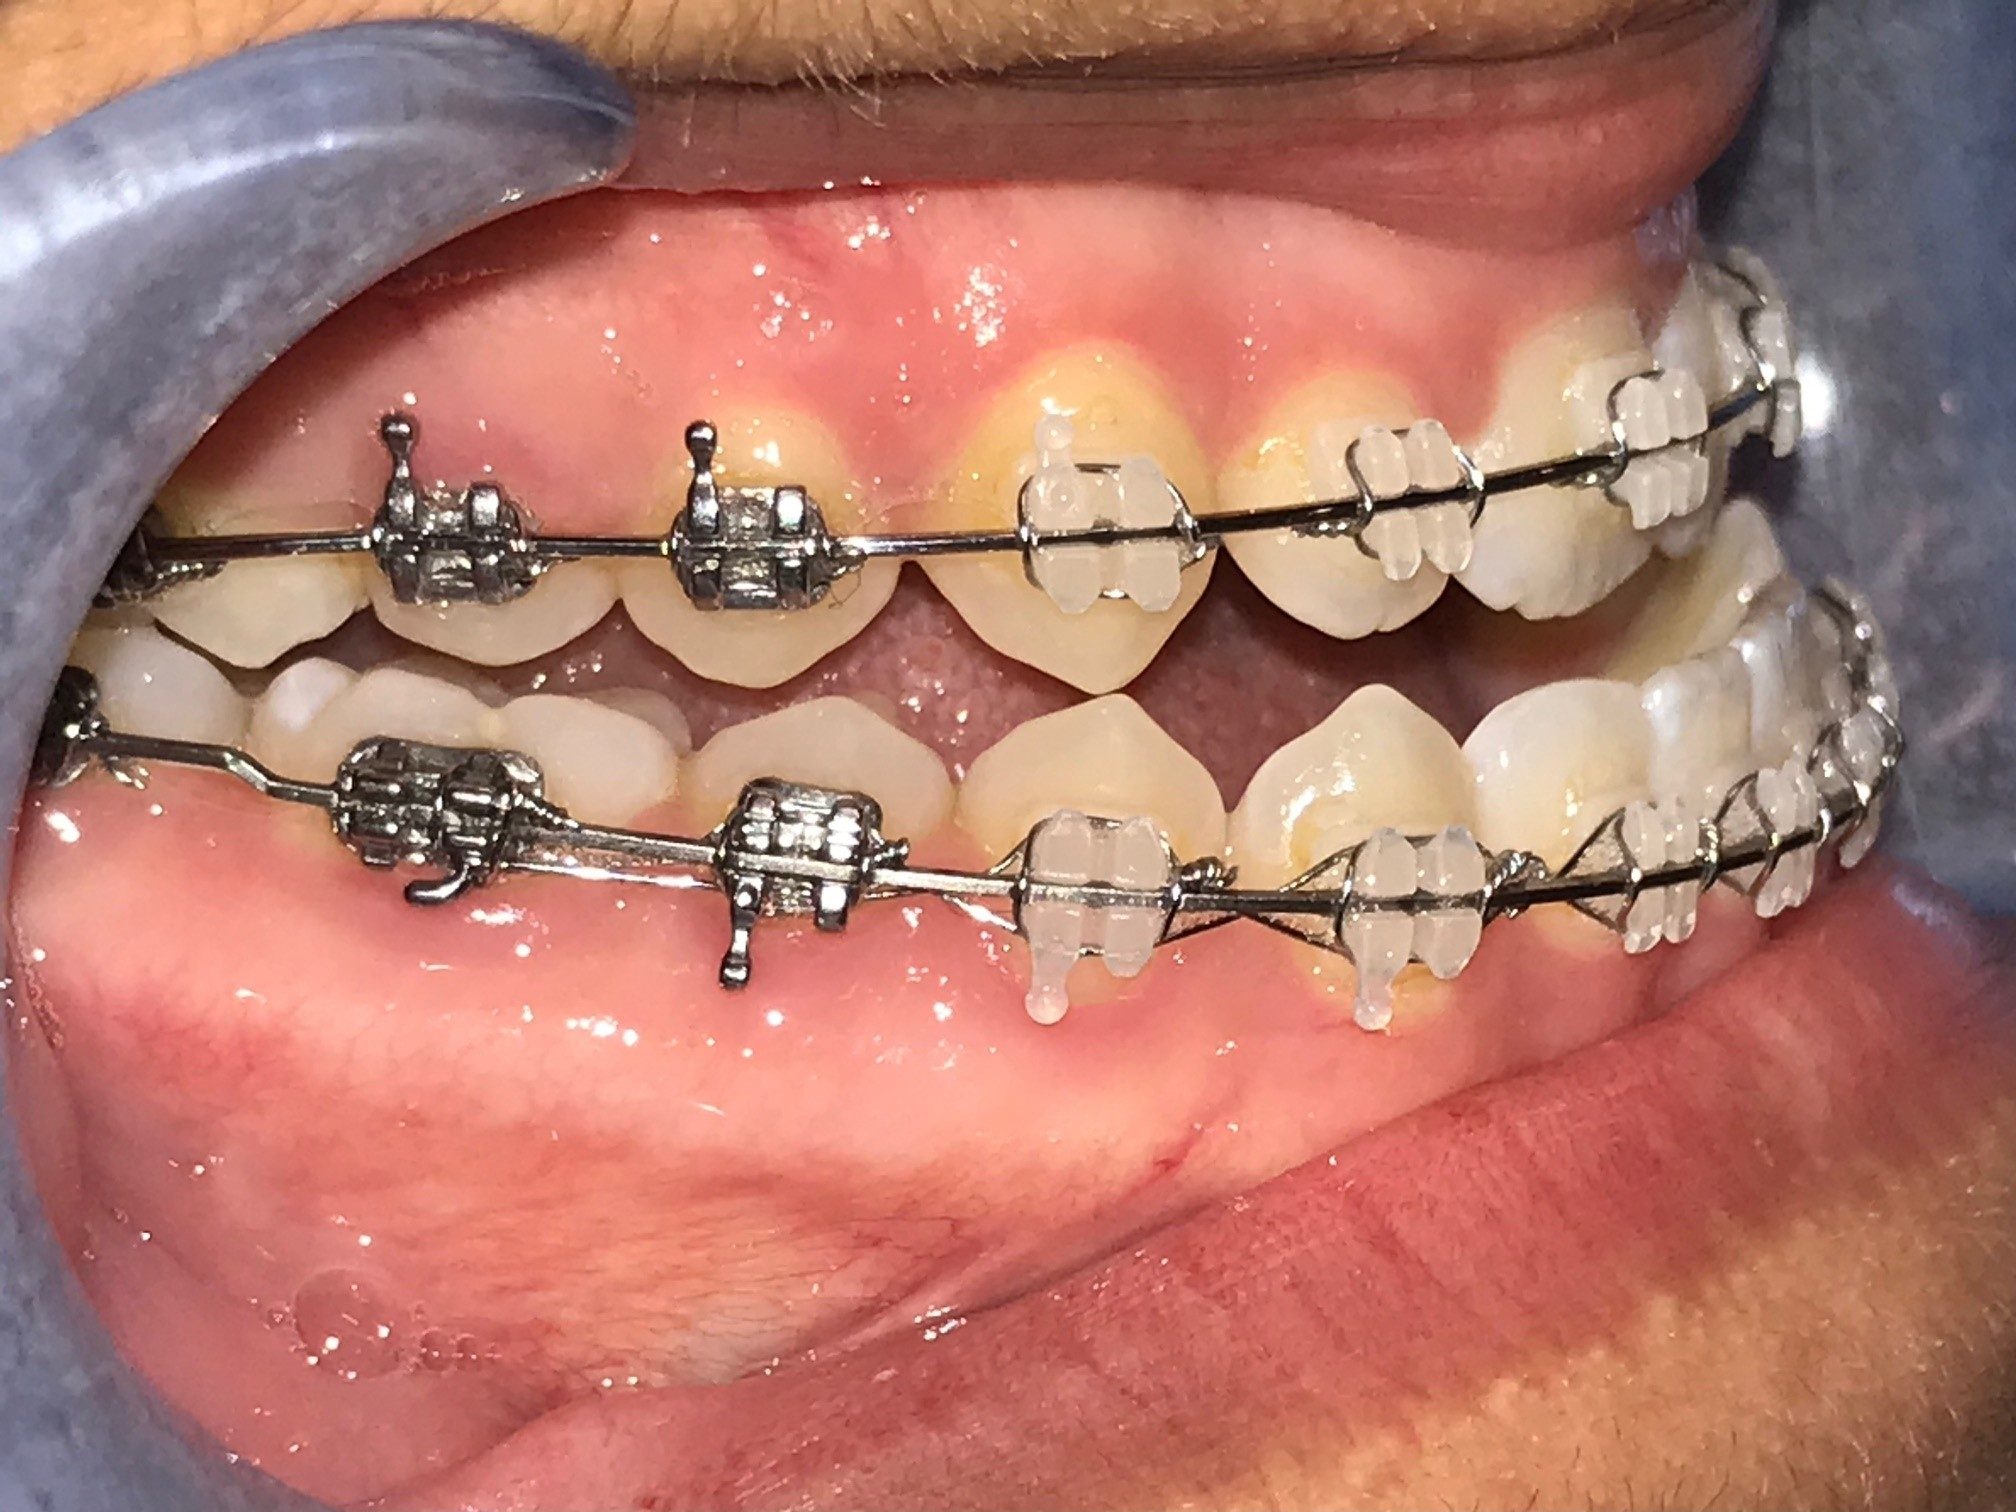

Avant la chirurgie

L’orthodontiste effectuera la phase de redressement et d’alignement de vos dents à l’aide d’appareils orthodontiques (broches ou gouttières Invisalign). Cette phase dure de 12 à 24 mois de façon générale. Au cours de cette période, il vous sera possible de nous revoir afin de répondre à vos questions si nécessaire.

De plus, les dents de sagesse devront être extraites afin de permettre une guérison complète de l’os avant d’effectuer la chirurgie orthognatique. Lorsque votre orthodontiste jugera votre alignement dentaire adéquat, il informera notre équipe.